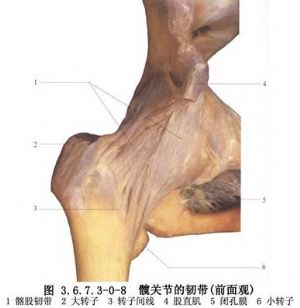

手術相關解剖見下圖(圖3.6.7.3-1~3.6.7.3-4)。